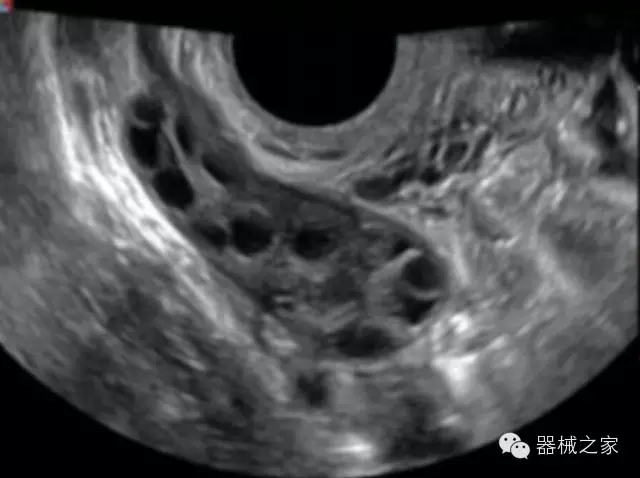

臨床圖片賞析

·全球目前唯一一款配備主機(jī)雙探頭接口,整機(jī)重量(含電池)在5公斤以內(nèi)的便攜式彩超;

·獨(dú)有的HoloTM PW 實時3取樣門PW成像技術(shù),精確進(jìn)行血管診斷;

·獨(dú)有的大角度及實時溫控技術(shù),能同一切面顯示宮頸及宮體,有效減低了患者的痛苦,及保護(hù)粘膜保證了醫(yī)療安全;